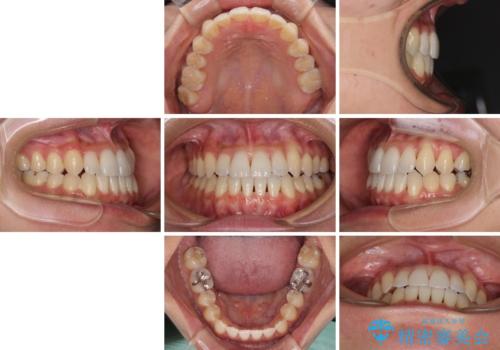

前歯のデコボコ インビザラインによる矯正治療

- 上下前歯の叢生と奥歯の反対咬合を気にして来院された患者様です。

インビザラインを用い、下顎はIPR(歯と歯の間を削る)と歯列全体を後方に移動させ、上顎は側方に拡大させることで歯列を改善していくこととしました。

骨格的に下顎が左側前方にずれているため、上下正中のズレや左右奥歯の咬み合わせを理想的な状態とすることは困難でした。